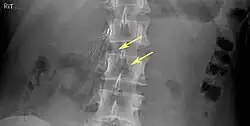

Of these IVC filter side effects, 328 involved device migration, 146 involved embolizations after detachment of device components, 70 involved perforation of the IVC, and 56 involved filter fracture. Much of the medical community believes that this large number of adverse events is related to the heart filter remaining in place for longer than necessary.

- Filter fracture

- Filter fracture: Broken struts migrate to retroperitoneum, requiring exploration.[21] Also struts can migrate to the heart and can cause pericardial effusion and tamponade.[22]